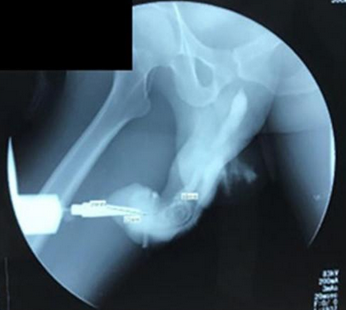

Während der Penis technisch gesehen knochenlos ist, wird das Wort "Bruch" verwendet, um einen Riss in der Tunica albuginea zu beschreiben - dem Gewebe, das es dem Penis ermöglicht, sich zu vergrößern und zu erigieren. Eine anschließende Untersuchung bestätigte, dass der Patient tatsächlich eine "breite und tiefe Fraktur des Penis" hatte und das Penisgewebe ebenfalls gerissen war. Die Studienautoren erklärten, dass solche Phallusfrakturen auftreten, wenn der erigierte Penis bei heftigen sexuellen Aktivitäten fest auf den Damm oder das Schambein aufschlägt.